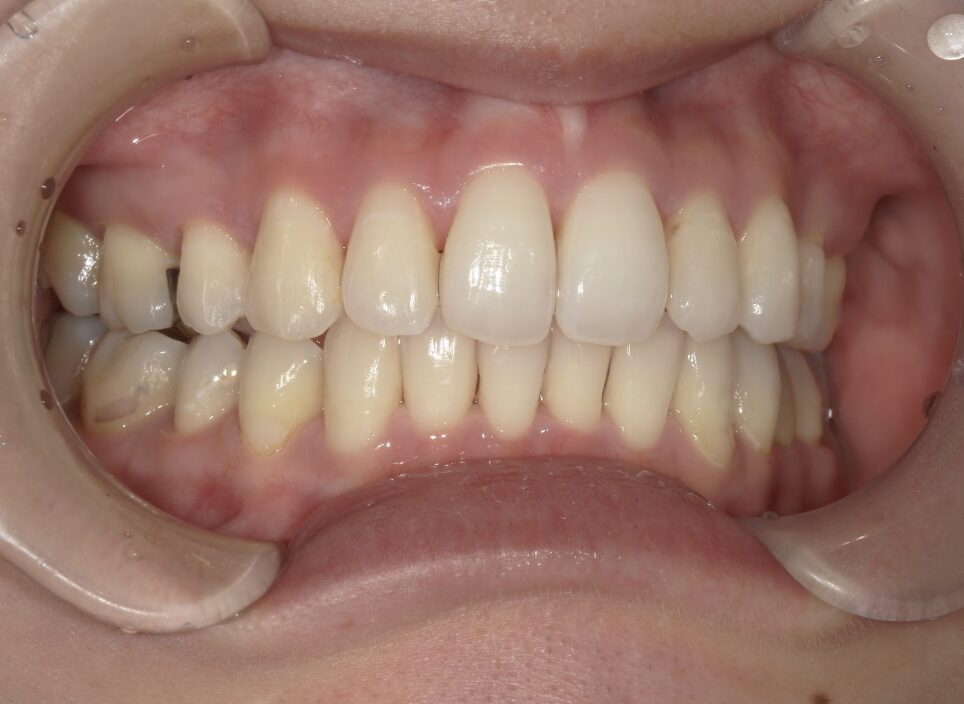

治療後

前歯が全く当たっていないを主訴に当院を受診され、開咬・上顎前突・下顎叢生を認めました。

上顎左右4番抜歯を行いIPRを使用してマウスピース型矯正装置(インビザライン)を使用し、改善を行いました。

治療期間1年9ヶ月